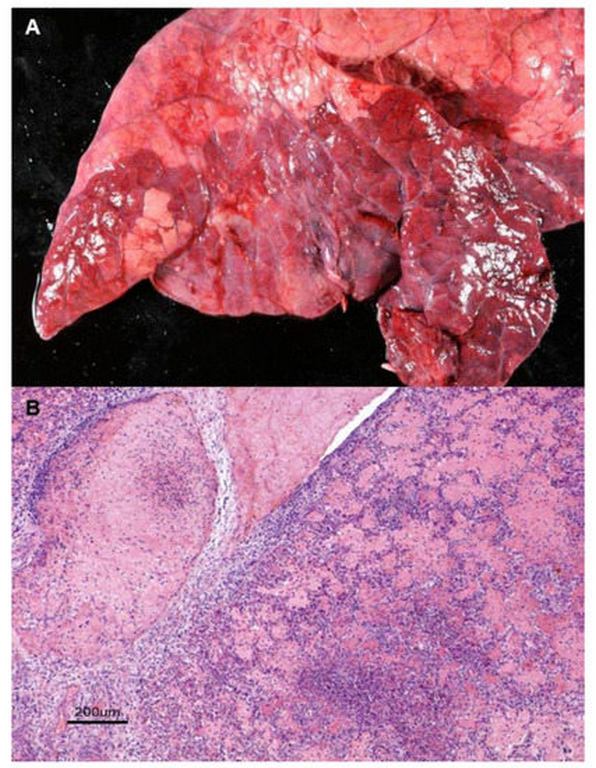

پاتوژنهای اصلی در بیماریهای تنفسی دام شامل مانهیمیا همولیتیکا، پاستورلا مولتیسیدا و انتروباکتر هورمائچی هستند. مانهیمیا همولیتیکا، یک باکتری گرم منفی و فرصتطلب، اغلب از مجاری تنفسی فوقانی به ریه منتقل میشود و با تولید لوکوتوکسین (Leukotoxin) و لیپوپلیساکارید، باعث آسیب بافتی، نکروز ایسکمیک(Ischemic necrosis) و التهاب فیبرینوز (Fibrinous inflammation) میگردد. سروتایپهای A1، A2 و A7 این باکتری در گوسفند و بز غالب هستند و از طریق روشهای مولکولی مانند واکنش زنجیرهای پلیمراز بر اساس ژن Rpt2 شناسایی میشوند. پاستورلا مولتوسیدا، اغلب همراه با مانهیمیا همولیتیکا عمل میکند و سروتایپ A آن در عفونتهای تنفسی شایع است. این باکتریها میتوانند در حیوانات ظاهراً سالم وجود داشته باشند اما تحت استرس فعال شوند. در گاو، انتروباکتر هورمائچی از کمپلکس باکتری های تنفسی جدا شده و با روشهای مولکولی مانند توالییابی ژن 16S rRNA تشخیص داده میشود. این باکتری مقاومت چنددارویی نشان میدهد و در عفونتهای تنفسی ثانویه نقش دارد. سایر پاتوژنها مانند هیستوفیلوس سومنی، مایکوپلاسما بوویس نیز درگیر هستند و اغلب عفونتهای پلیمیکروبیال ایجاد میکنند.